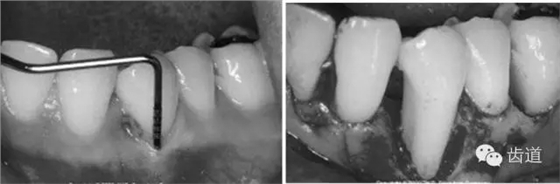

5、膜材料的邊緣位置和固位

原則是生物膜能充分覆蓋病損區(qū)。冠方緊鄰釉牙骨質(zhì)界,根方伸展至骨邊緣下2~3mm,保證在組織愈合過(guò)程中能確切阻止口腔上皮和牙齦結(jié)締組織與牙根面接觸。

當(dāng)生物膜放置就位后,為防止受齦瓣的擠壓而移位后影響療效,應(yīng)用細(xì)線穿過(guò)生物膜的上部邊緣使之緊緊環(huán)抱牙齒,并采用懸吊縫合將其固定于牙面上。